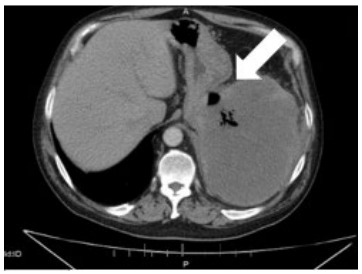

Introduction: A gastrosplenic fistula (GSF) is a pathologic connection between the spleen and stomach that can lead to life-threatening complications. A GSF can arise spontaneously but is often secondary to a variety of etiologies. Most commonly, GSFs arise from gastric or splenic non-Hodgkin diffuse large B-cell lymphomas (DLBCL). Only 46 cases of GSFs have been published to date, and due to its rarity extensive literature review is insufficient for characterization of GSFs.

Case report: This case discusses a patient with intermittent abdominal pain and weight loss, which led to the diagnosis and treatment of a GSF and DLBCL. The patient later went into remission for his DLBCL but succumbed to respiratory failure from a secondary abdominal-pleural fistula formation. Gastrosplenic fistulas have the potential to cause fatal, massive, upper gastrointestinal hemorrhages, infections, other fistulas, or esophageal obstructions. A delay in diagnosis corresponds with a higher morbidity and mortality; thus, prompt detection and treatment are imperative. The management of GSFs is complex and requires a multidisciplinary approach to care.